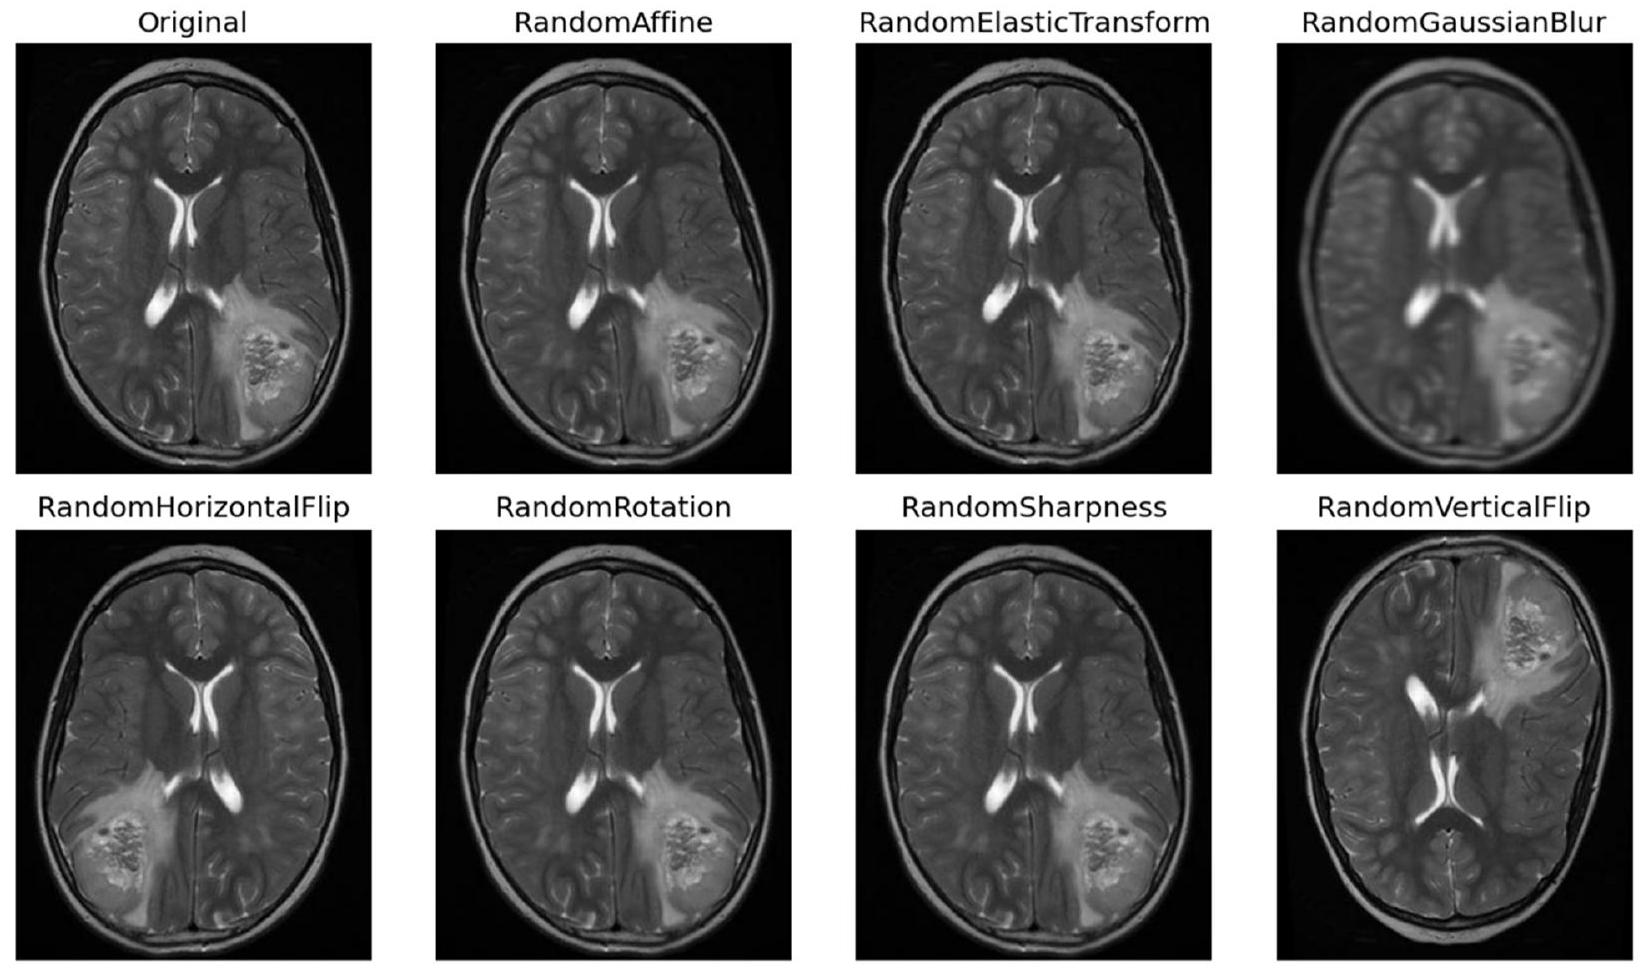

تُصبح التقنيات ضرورية لتعزيز ثراء مجموعة البيانات، مما يزيد من قوة النموذج وقدراته على التعميم. تشمل منهجيات التAugmentation مجموعة من العمليات التحويلية، كل منها مصمم لإدخال تنوعات مختلفة تعكس سيناريوهات الأورام في العالم الحقيقي. تُعتبر التدوير تقنية أساسية، حيث تسهل إنشاء صور من زوايا متعددة لمحاكاة المنظورات المتنوعة التي يتم مواجهتها في التصوير السريري [20]. في الشكل 5، تُظهر بعض الصور المعززة.

بالإضافة إلى ذلك، فإن عمليات التدوير أفقيًا ورأسيًا تنوع اتجاهات الصور، مما يحاكي بشكل فعال الترتيبات المكانية المتنوعة للأورام داخل الدماغ. تساهم عمليات تغيير الحجم أيضًا من خلال تغيير حجم الصور لمحاكاة طيف أحجام الأورام التي يتم مواجهتها في الممارسة السريرية، مما يعزز قدرة النموذج على تمييز الأورام ذات الأبعاد المختلفة. تعمل عمليات الترجمة، سواء عموديًا أو أفقيًا، على إزاحة الصور مكانيًا لتدريب النموذج على تحديد موقع الأورام، بغض النظر عن موقعها داخل الدماغ. توضح الشكل 6 صورة واحدة بعد خطوات مختلفة.

techniques becomes imperative to bolster the dataset’s richness, thereby augmenting the model’s robustness and generalization capabilities. These augmentation methodologies encompass a range of transformative processes, each designed to introduce diverse variations reflective of real-world tumor scenarios. Rotation serves as a foundational technique, facilitating the generation of images from multiple angles to emulate the diverse perspectives encountered in clinical imaging [20]. In Fig. 5 some augmented images are shown.

In conjunction, flipping operations horizontally and vertically diversify image orientations, effectively mimicking the varying spatial arrangements of tumors within the brain. Scaling manipulations further contribute by resizing images to simulate the spectrum of tumor sizes encountered in clinical practice, thereby enhancing the model’s ability to discern tumors of varying dimensions. Translation operations, both vertically and horizontally, spatially displace images to train the model in tumor localization, regardless of their position within the brain. Figure 6 shows one image after different steps.